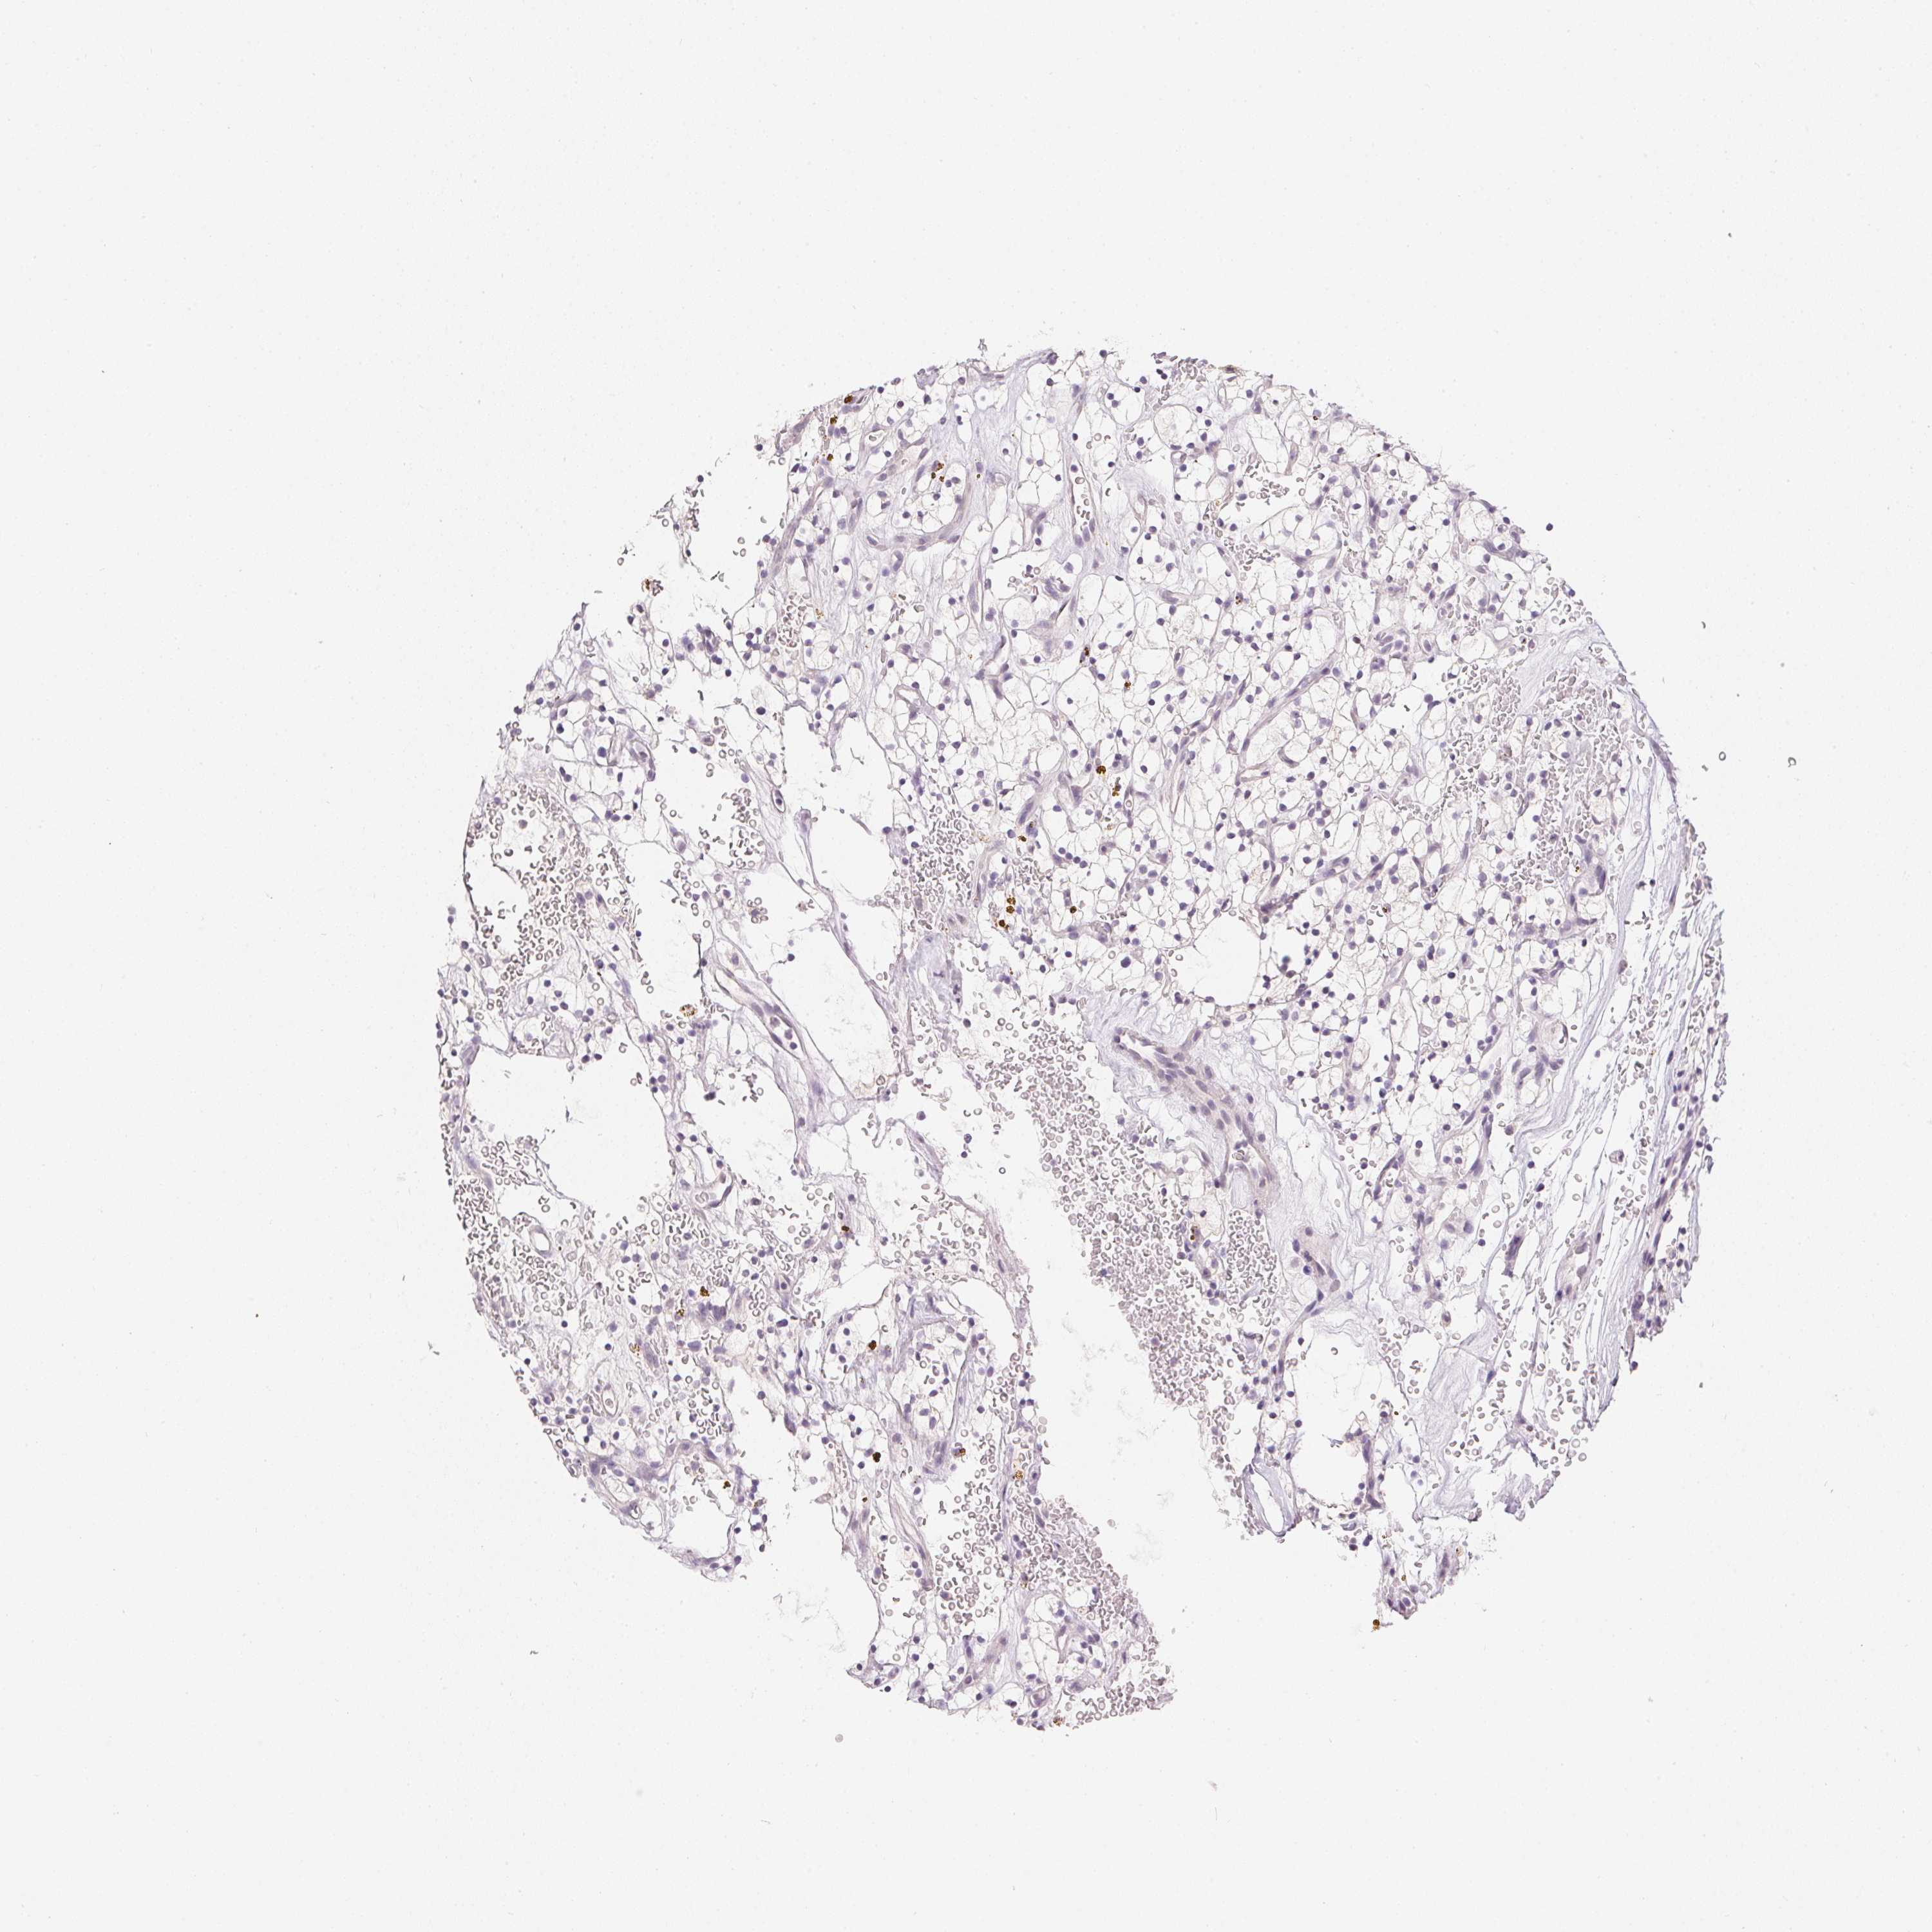

TCGA RNA samplesi

RNA-seq data is reported as average FPKM (number Fragments Per Kilobase of exon per Million reads), generated by the The Cancer Genome Atlas (TCGA) .

Normal distribution across the dataset is visualized with box plots, shown as median and 25th and 75th percentiles. Points are displayed as outliers if they are above or below 1.5 times the interquartile range. FPKM values of the individual samples are presented next to the box plot.

Average pTPM 0.0

Number of samples 100